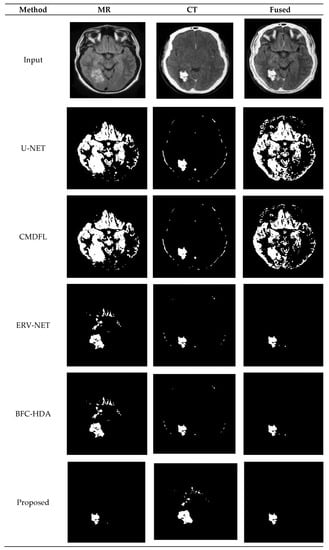

| Method | SACC | SSEN | SPEC | SPR | SNPV | SFPR | SFDR | SFNR | SF1 | SMCC |

|---|---|---|---|---|---|---|---|---|---|---|

| U-NET [20] | 90.17 | 90.39 | 90.53 | 93.03 | 90.81 | 90.64 | 90.51 | 94.19 | 91.38 | 94.17 |

| CMDFL [22] | 91.2 | 90.67 | 91.94 | 93.41 | 92.53 | 92.62 | 90.86 | 94.82 | 93.12 | 95.51 |

| ERV-NET [23] | 93.33 | 94.12 | 92.59 | 94.04 | 93.33 | 95.93 | 92.53 | 97.11 | 94.97 | 97.56 |

| BFC-HDA [27] | 96.45 | 98.32 | 96.65 | 95.15 | 95.88 | 98.78 | 96.14 | 98.13 | 97.9 | 97.99 |

| HFCMIK | 99.76 | 99.11 | 98.19 | 99.59 | 98.88 | 98.89 | 98.99 | 99.92 | 99.43 | 99.93 |